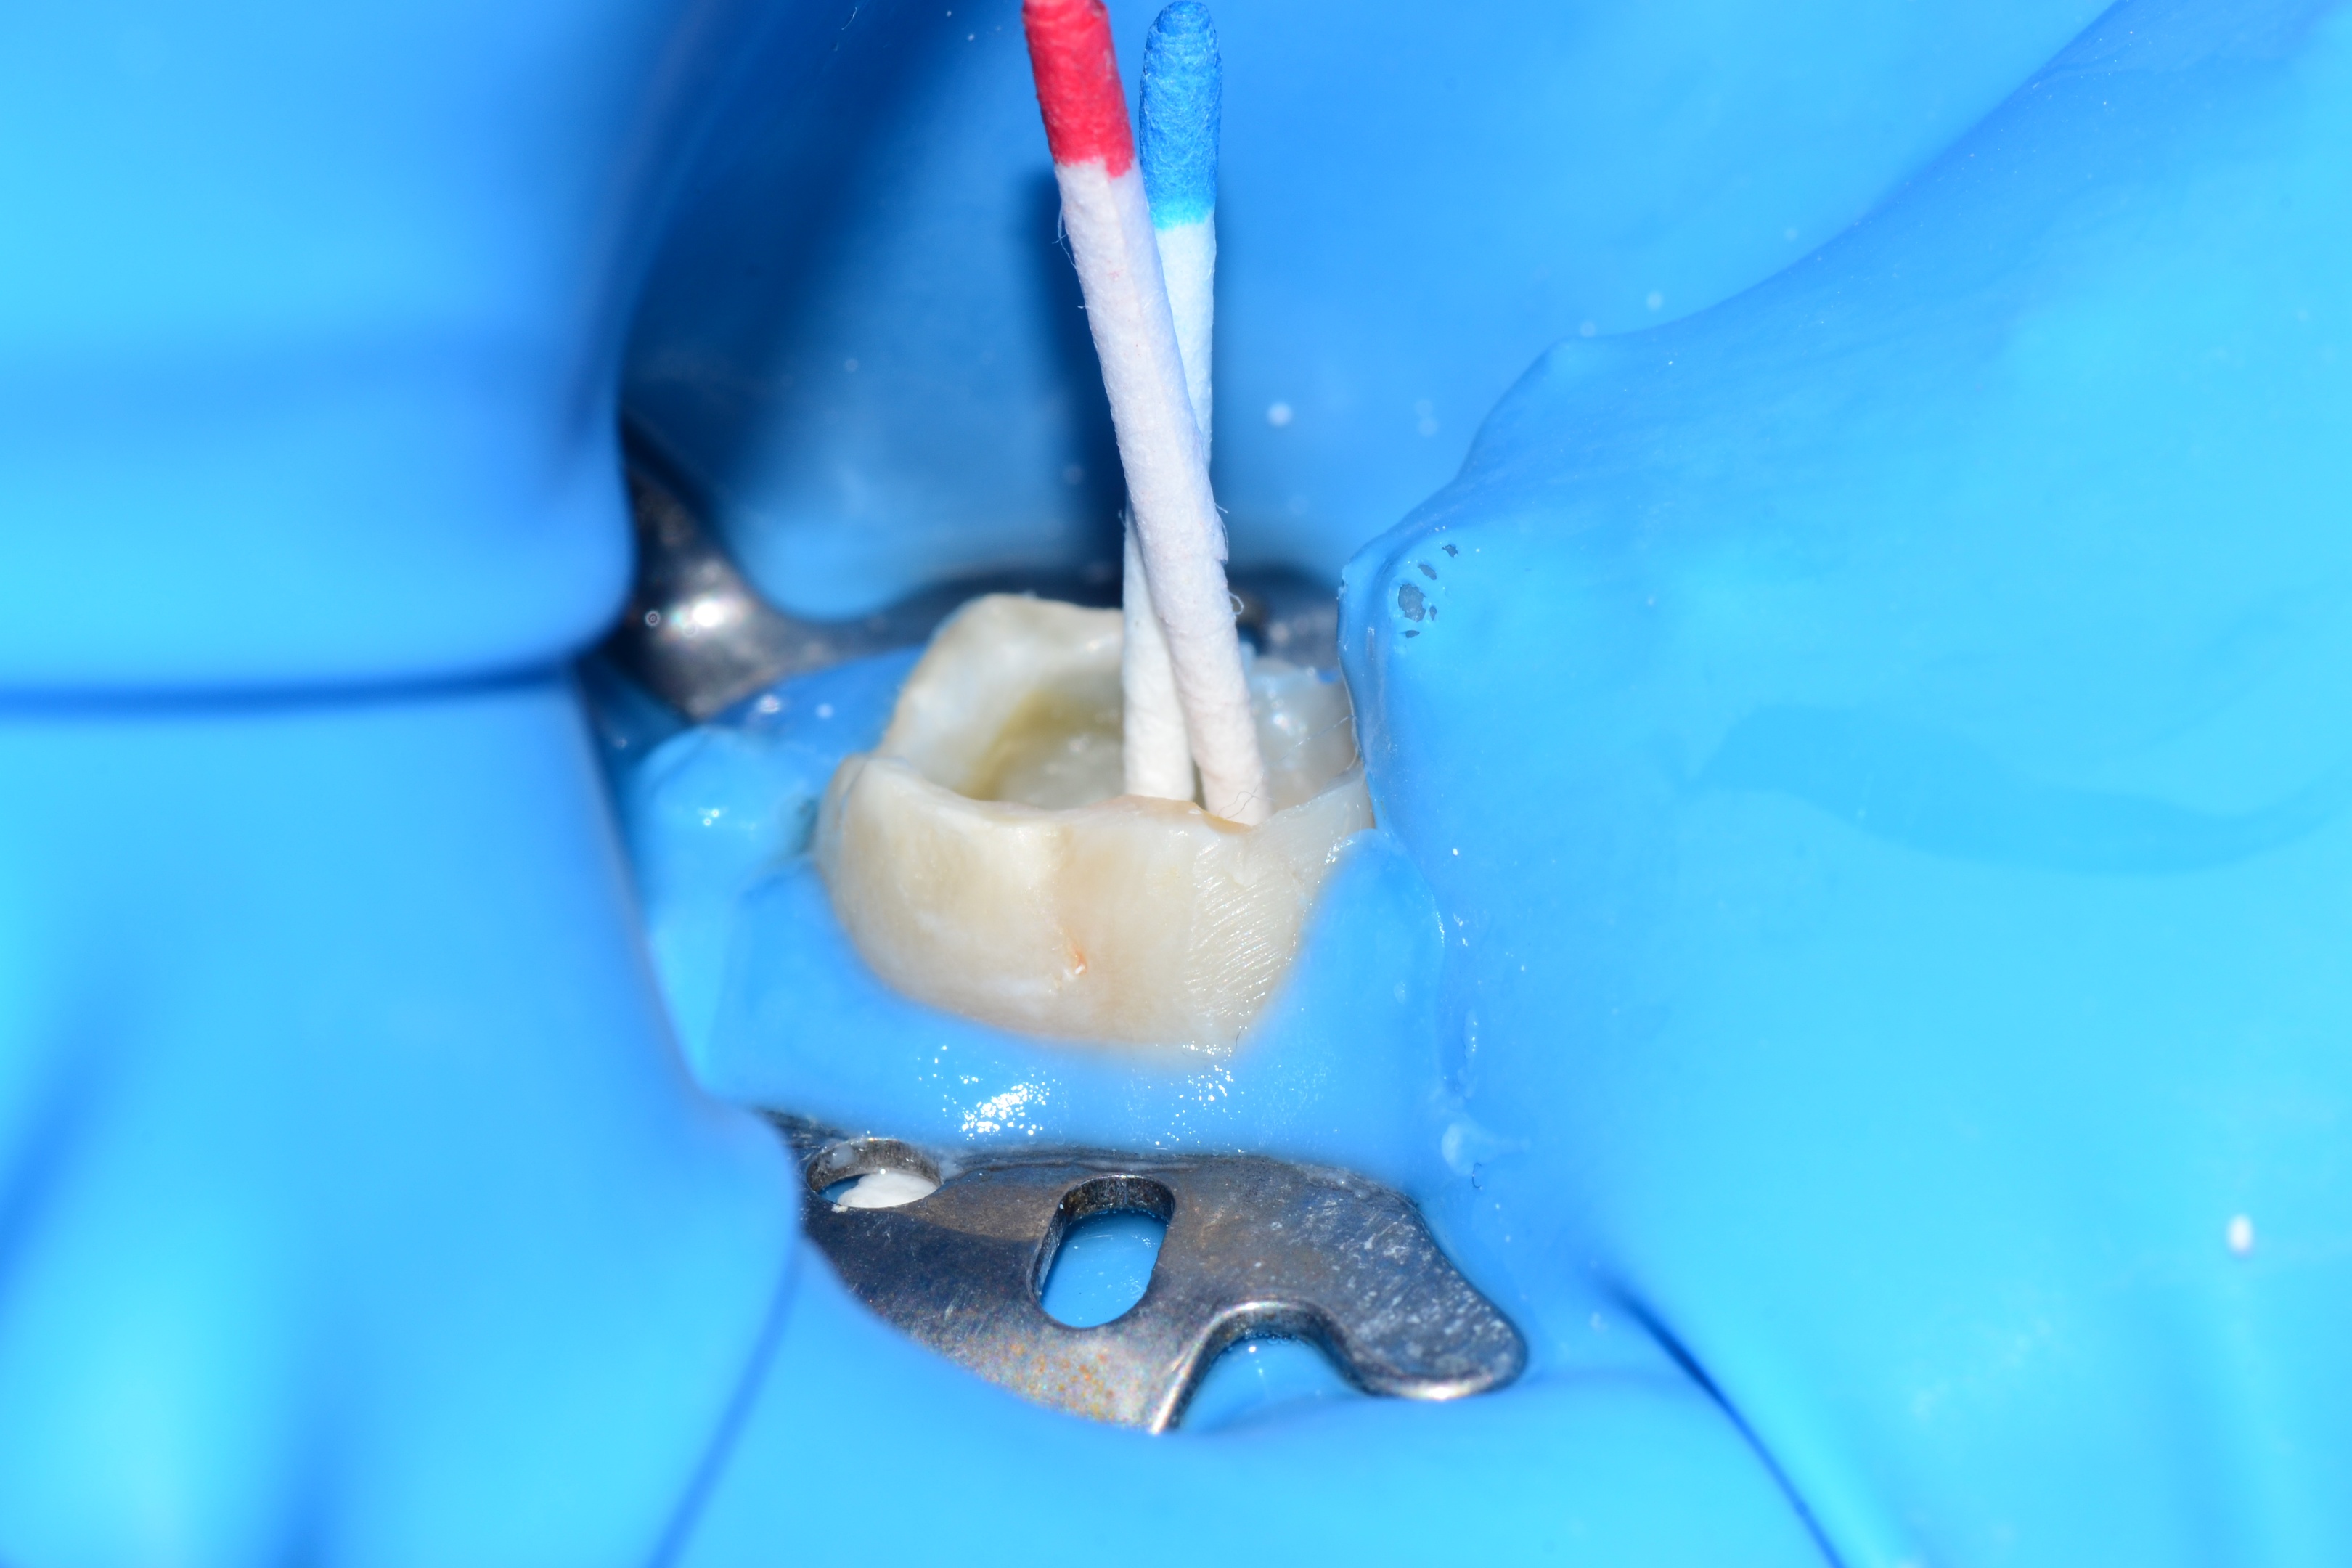

Rešenje za to postoji i naziva se koferdam (engl. Rubberdam). U osnovi predstavlja gumu koja se nanosi oko zuba koji se popravljaju. U gumi se napravi rupica, a kroz tu rupicu provuče zub. Ovo se sve fiksira kvačicom i tako izolujemo zub od pljuvačke, ali još bitnije, izolujemo usta od dosadne vode i neprijatnih tečnosti.

Još neke od prednosti koferdama su sprečavanje prolaska sitnih instrumenata ka grlu, ali i osiguravanje da nadoknade traju duže, baš zbog apsolutne izolacije zuba koji radimo.

Najčešće intervencije kod kojih se koristi koferdam su lečenja zuba, plombiranja zuba, ali i cementiranja krunica.